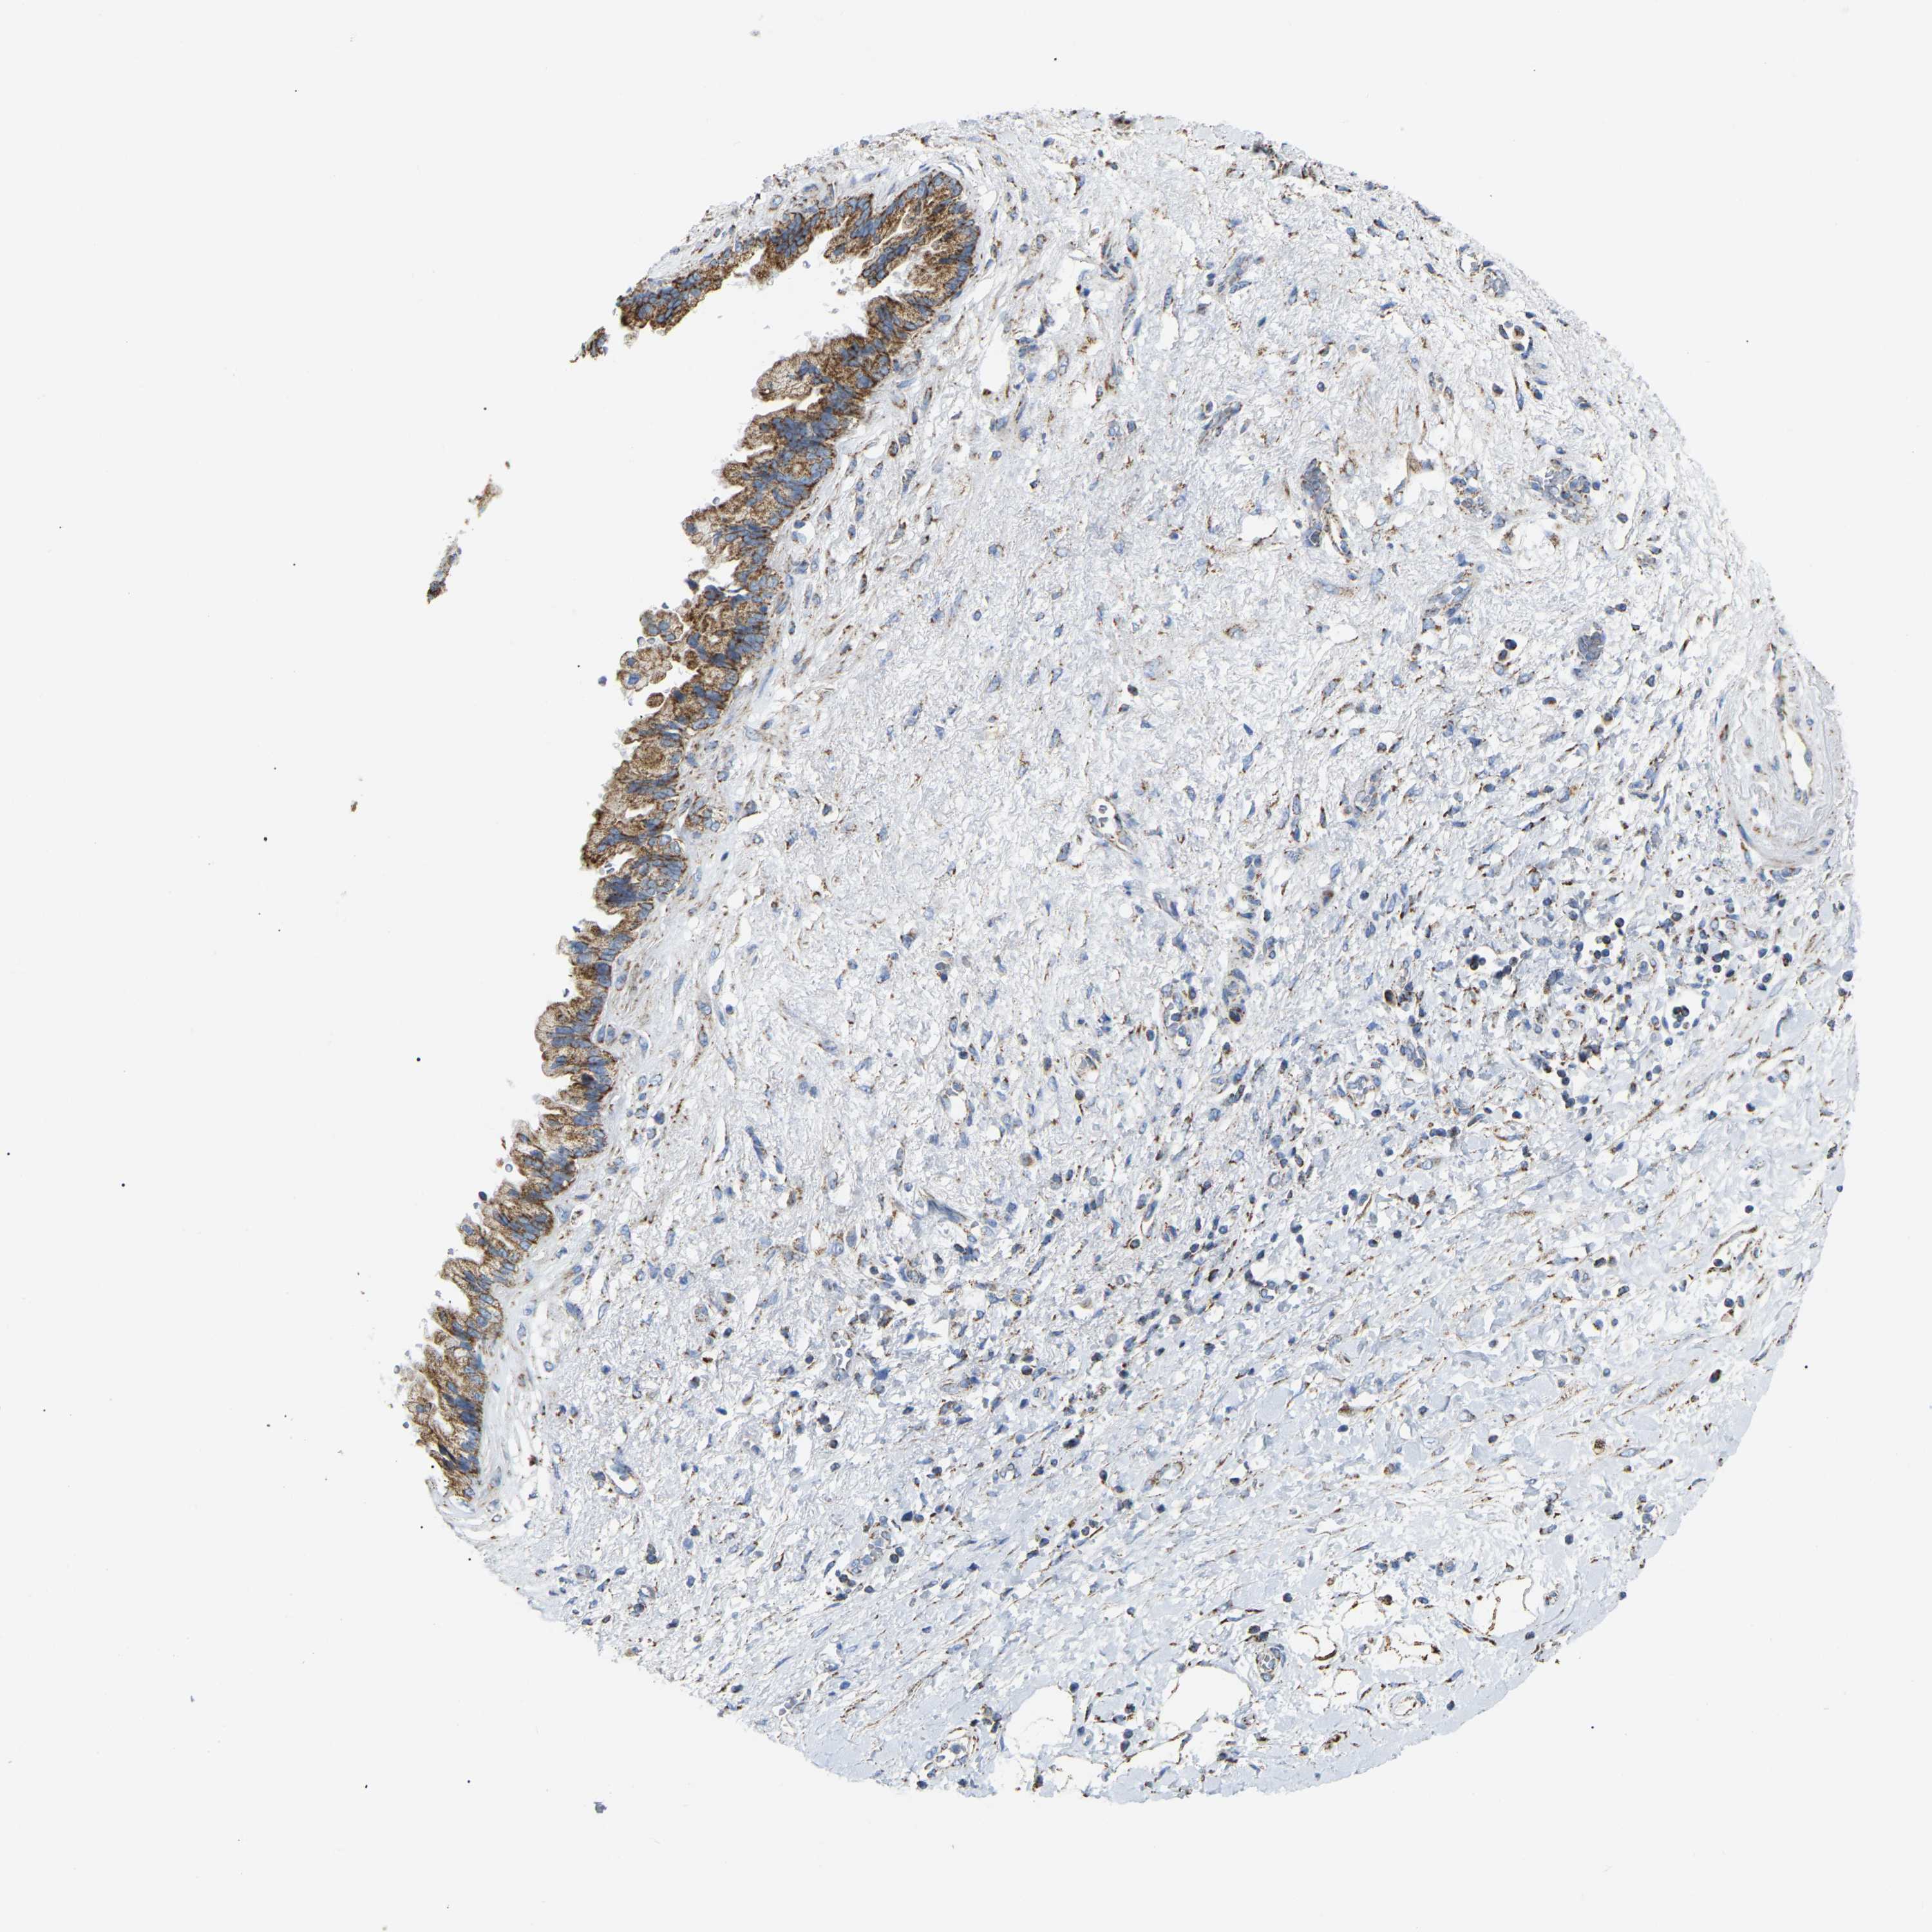

PANCREATIC CANCER - Protein expressioni

A mouse-over function shows sample information and annotation data. Click on an image to view it in a full screen mode. Samples can be filtered based on level of antibody staining by selecting one or several of the following categories: high, medium, low and not detected. The assay and annotation is described here.

Note that samples used for immunohistochemistry by the Human Protein Atlas do not correspond to samples in the TCGA dataset.

Antibody stainingi

Antibody staining in the annotated cell types in the current human tissue is reported as not detected, low, medium, or high, based on conventional immunohistochemistry profiling in selected tissues. This score is based on the combination of the staining intensity and fraction of stained cells.

Each image is clickable and will lead to virtual microscopy that enables deeper exploration of all samples and also displays staining intensity scores, fraction scores and subcellular localization as well as patient and tissue information for each sample.

Antibody HPA019522

Antibody HPA021002

Staining

High

Medium

Low

Not detected

Intensity

Strong

Moderate

Weak

Negative

Quantity

>75%

75%-25%

<25%

None

Location

Nuclear

Cytoplasmic/membranous

Cytoplasmic/membranous,nuclear

Adenocarcinoma, NOS